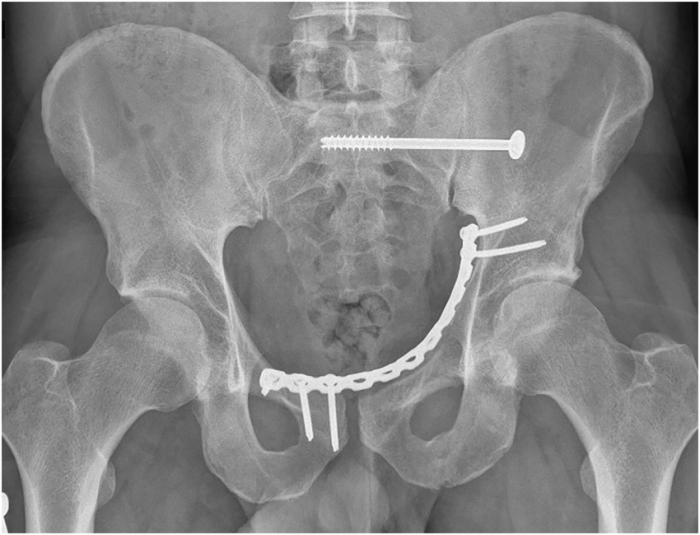

I'm working on a story where a character has a pelvic fracture, and no, it's not one of those weird medical fetish things, I promise! But I need to mention him getting a pelvic binder (which he gets prehospital) and a foley catheter. My research says that combination makes sense? It'll likely be in dialogue of a Dr ordering it and then it's just implied that this works out, or otherwise a short mention- so I don't need to describe the details. I could hand-wave it away entirely, not mention it at all. But now it's like this annoying brain gremlin I can't shake: I've been obsessively looking at pictures of these binder things, scratching my head, thinking "How- physically, logistically, spiritually, how?" Have I lost all understanding of male anatomy? Some of those binder things are wide! It's been driving me nuts for weeks and I can't just ask someone without sounding like a weirdo. 😅 Help!